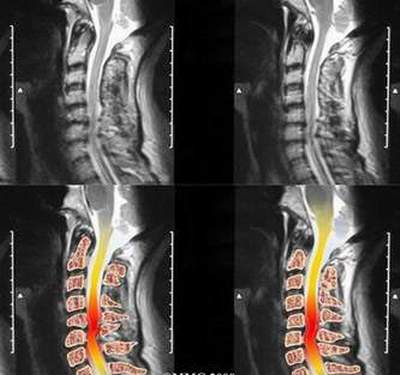

Tủy sống bắt đầu ở trên tại ngay lỗ lớn xương chẩm nơi tiếp cận với hành não và tận cùng ở dưới ngang mức bờ dưới đốt sống thắt lưng thứ nhất. Trên dọc chiều dài của tủy được gắn với 31 đôi dây thần kinh sống, mỗi dây được gắn với tủy sống qua một rễ trước (rễ vận động) và một rễ sau (rễ cảm giác).

Rối loạn cổ có rất nhiều nguyên nhân như gai xương, thoát vị đĩa đệm, chèn ép tăng động cột sống... do mang vật nặng, ngồi lâu trước máy (lái xe, xem tivi, vi tính), làm việc với thiết bị rung mạnh, kể cả hút thuốc... đột nhiên thấy cứng và đau cổ, có thể một bên hoặc hai bên, đối xứng hoặc không, có thể đau lan ra tay, mặt có thể lệch về một bên. Người bệnh khó thay đổi tư thế cổ vì đau, muốn nhìn về phía nào đó phải quay cả người...

Bệnh lý cổ có thể bán cấp do thoái hóa cột sống dần dà kết hợp với chấn thương nhẹ hoặc lao động quá mức gây ra, dùng thuốc (một loại giảm đau và kết hợp một loại giãn cơ) và tập luyện, bệnh sẽ thuyên giảm nhanh chóng, hiếm tiến triển thành bệnh lý tủy. Tuy nhiên đa số người không chữa trị và luyện tập đều đặn, đến nơi đến chốn có thể có triệu chứng dai dẳng. Trường hợp bệnh lý rễ nặng, giảm chức năng vận động cần phải được phẫu thuật.